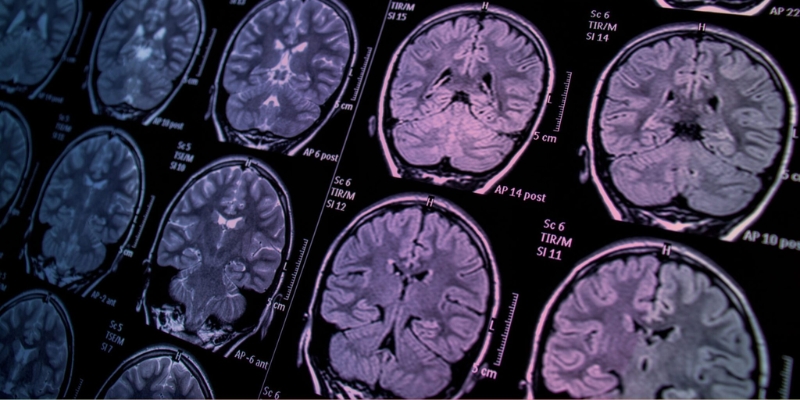

AI-powered medical imaging analysis

Computer vision has revolutionized medical imaging by automating the detection and interpretation of abnormalities in X-rays, CT scans, MRIs, and ultrasounds. Using this technology, radiologists can process vast amounts of data in seconds, highlighting subtle irregularities that may be missed by the human eye.

These AI-based diagnostics systems improve accuracy, speed up clinical workflows, and enable earlier intervention. Hospitals leveraging radiology automation also benefit from reduced manual workload and more consistent results, improving both efficiency and patient outcomes.